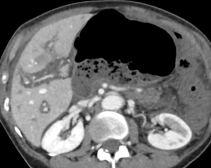

Non-cirrhotic hepatic dysmorphia- Hepatic steatosis – advanced level

- Vascular liver diseases - clinical cases – advanced level

- Benign liver tumors – advanced level

- Liver metastases – advanced level

- How to use hepatospecific contrast agents – advanced level

- Contrast-enhanced liver ultrasound